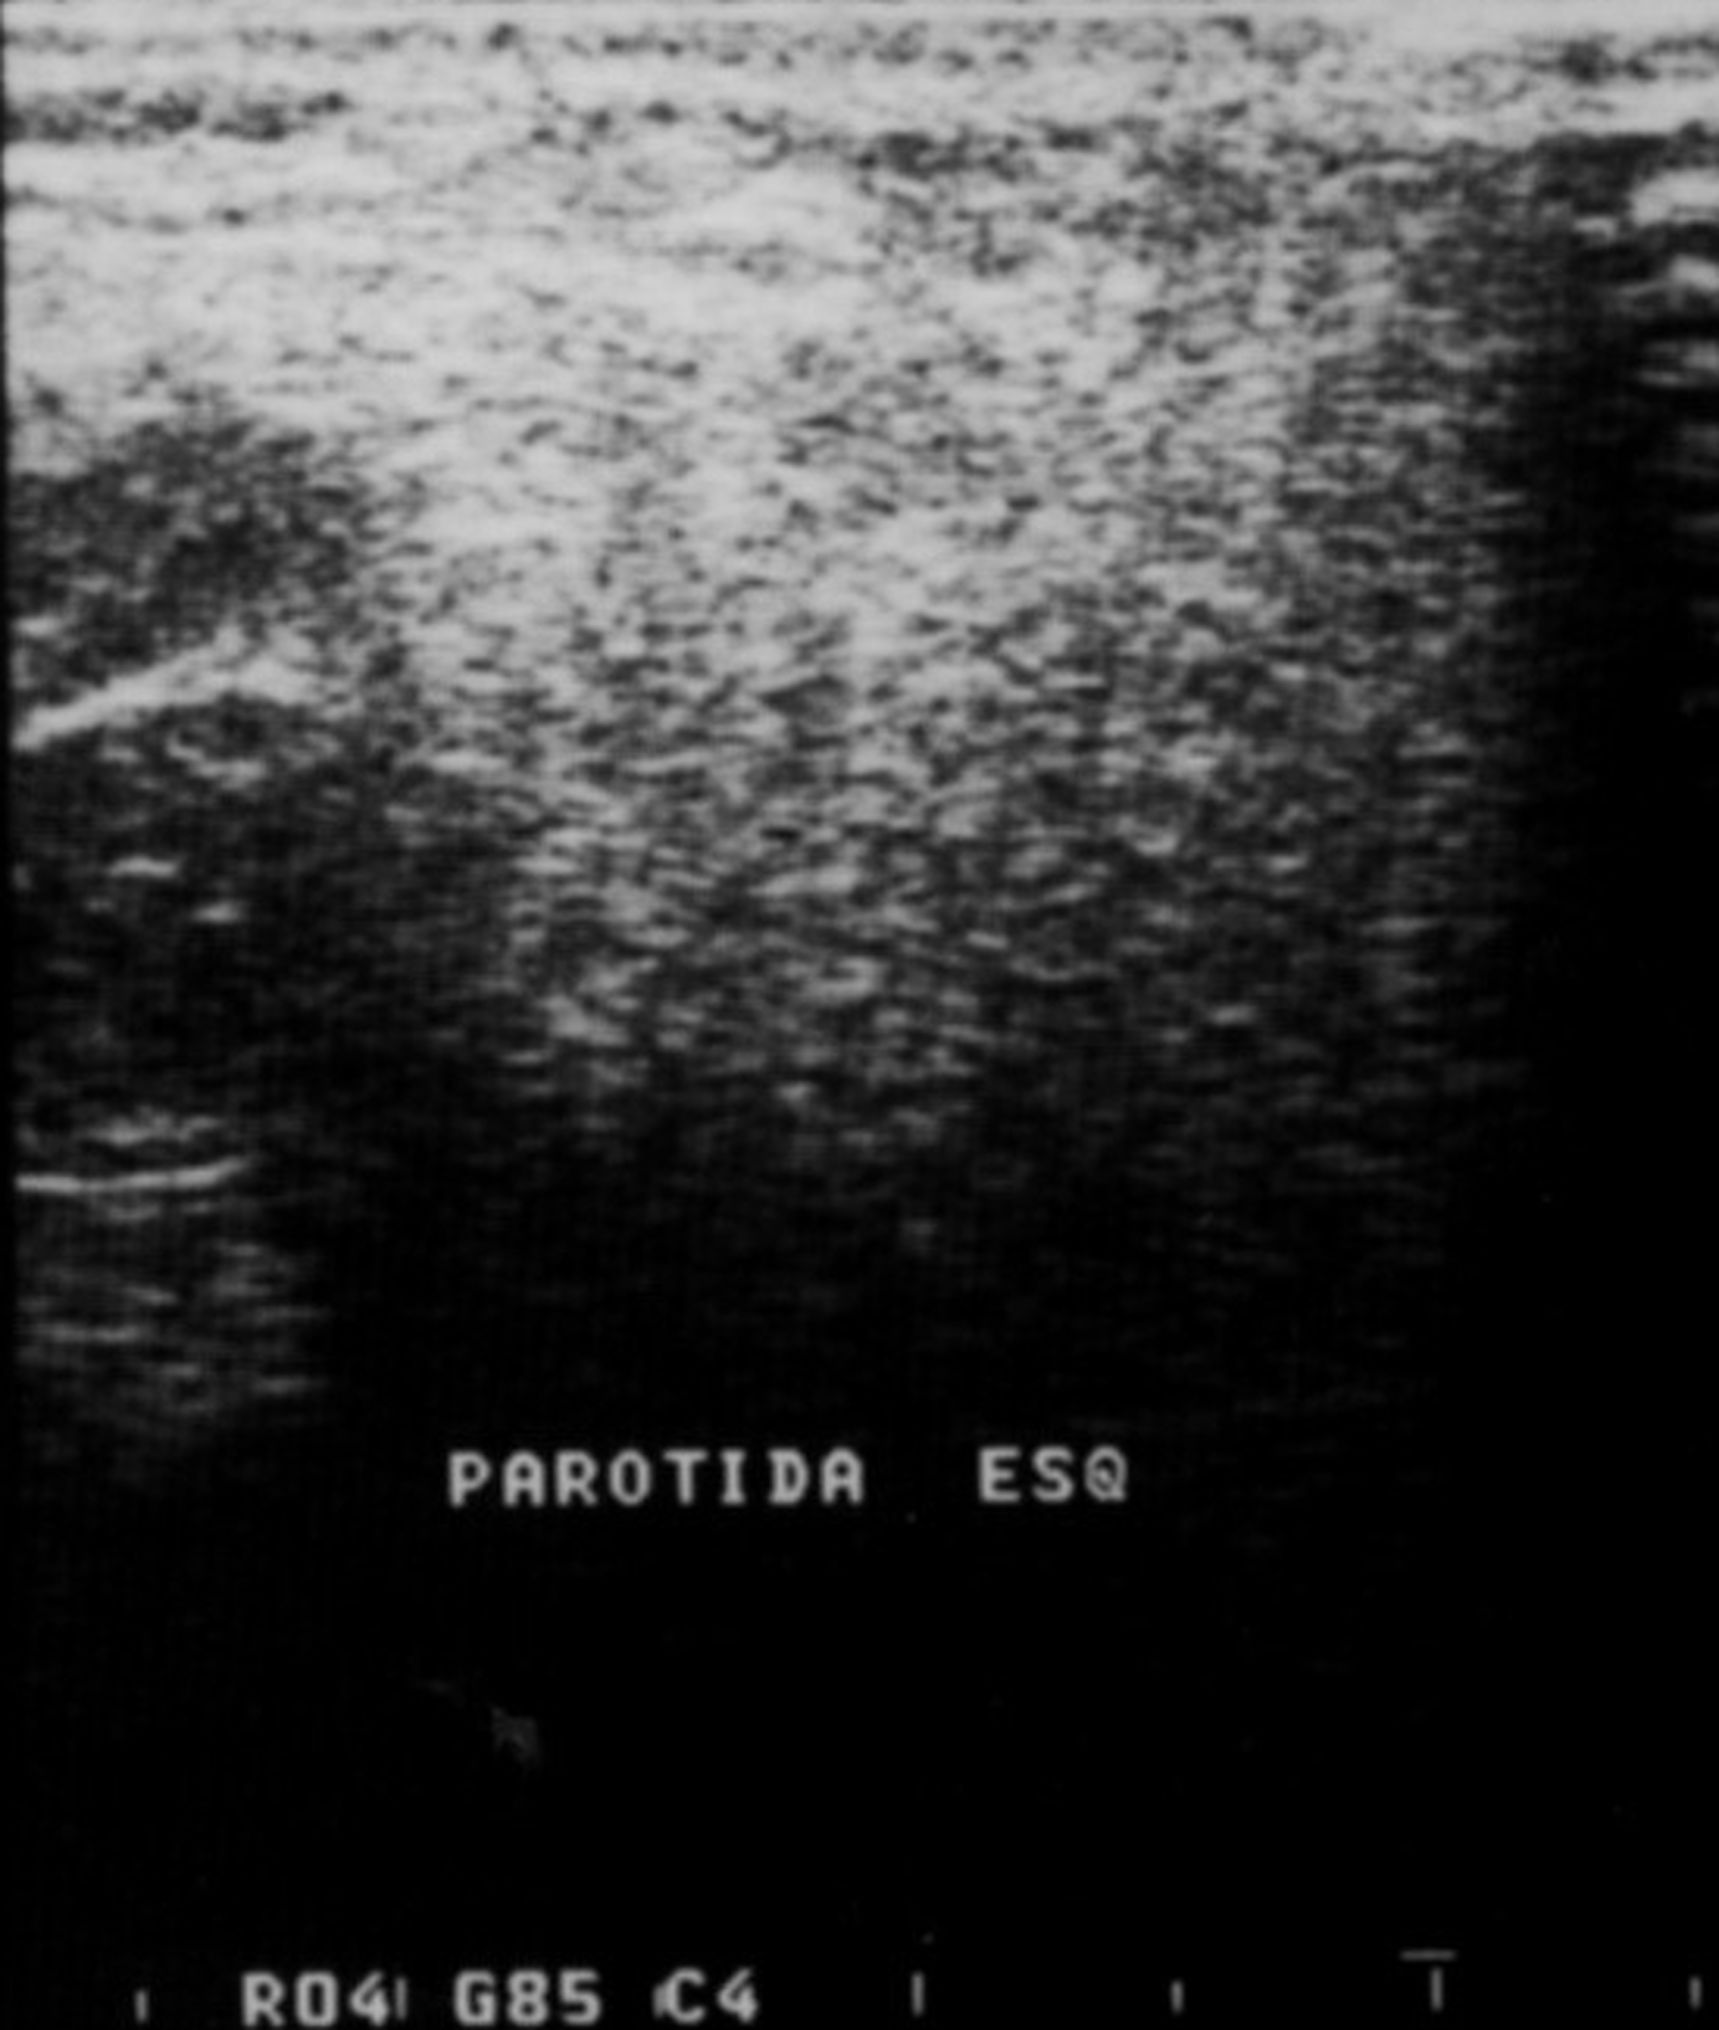

Imaging analyses, including ultrasonography and sialography, of the parotid glands were performed. Ultrasonographic features of the cervical region did not show any alterations of the submandibular and left parotid glands (Figure 2 through Figure 5). However, the right parotid gland demonstrated an inhomogeneous structure of the gland with scattered, multiple, small, oval, hypoechoic, or anechoic areas, usually well defined, and increased parenchymal blood flow. Sialographic examination of the right parotid gland showed a snowflake-like form and Christmas-tree pattern and evidence of sialoangiectasia without any changes of duct anatomy (Figure 6). Even after the salivary stimulation, the duct system was kept filled by the contrast fluid that again highlighted the sialectatic changes (Figure 7).

Fig 3. Sonogram of the left parotid gland showing normal pattern.

Figure 3